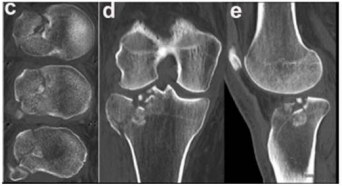

Caso clínico para responder à questão.

Um paciente de 39 anos de idade, vítima de queda de bicicleta, sofreu trauma no joelho direito. Foi levado ao pronto-socorro do hospital mais próximo, onde foram realizadas as radiografias apresentadas.